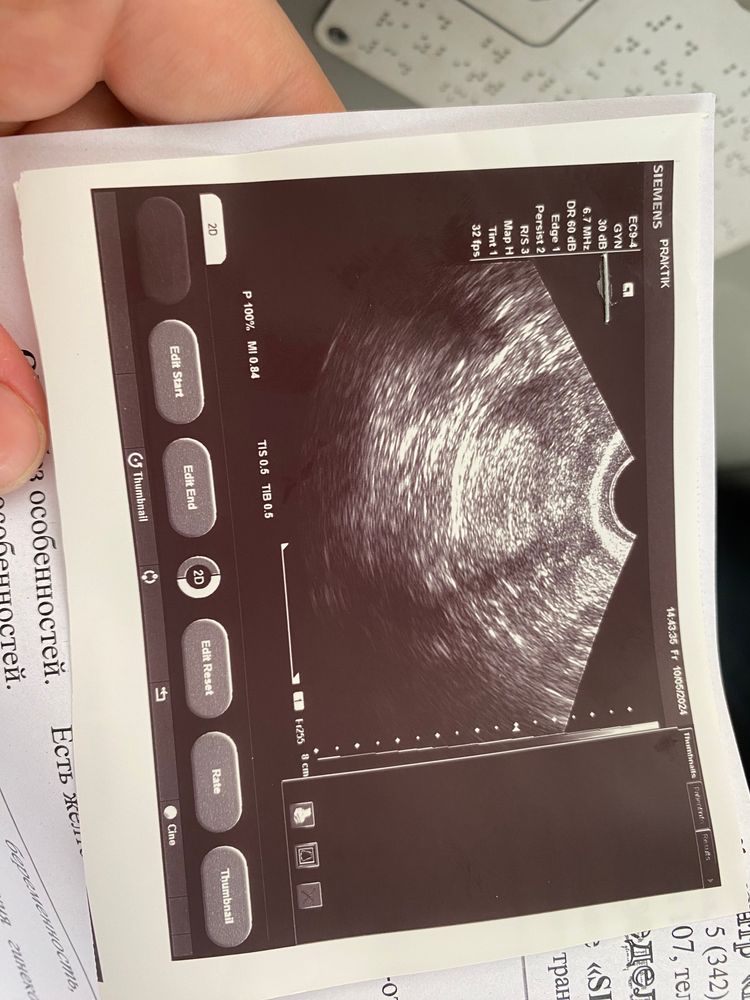

УЗИ на ранних сроках

А почему написали 1 плодное яйцо в матке , не визуализируется ? А как тогда поняли , что оно 1 и что оно в матке и что оно есть , если оно не визуализируется?

Очень странное заключение... 1 ПЯ ... Которое не визуализируется... Сходите к другому узисту.